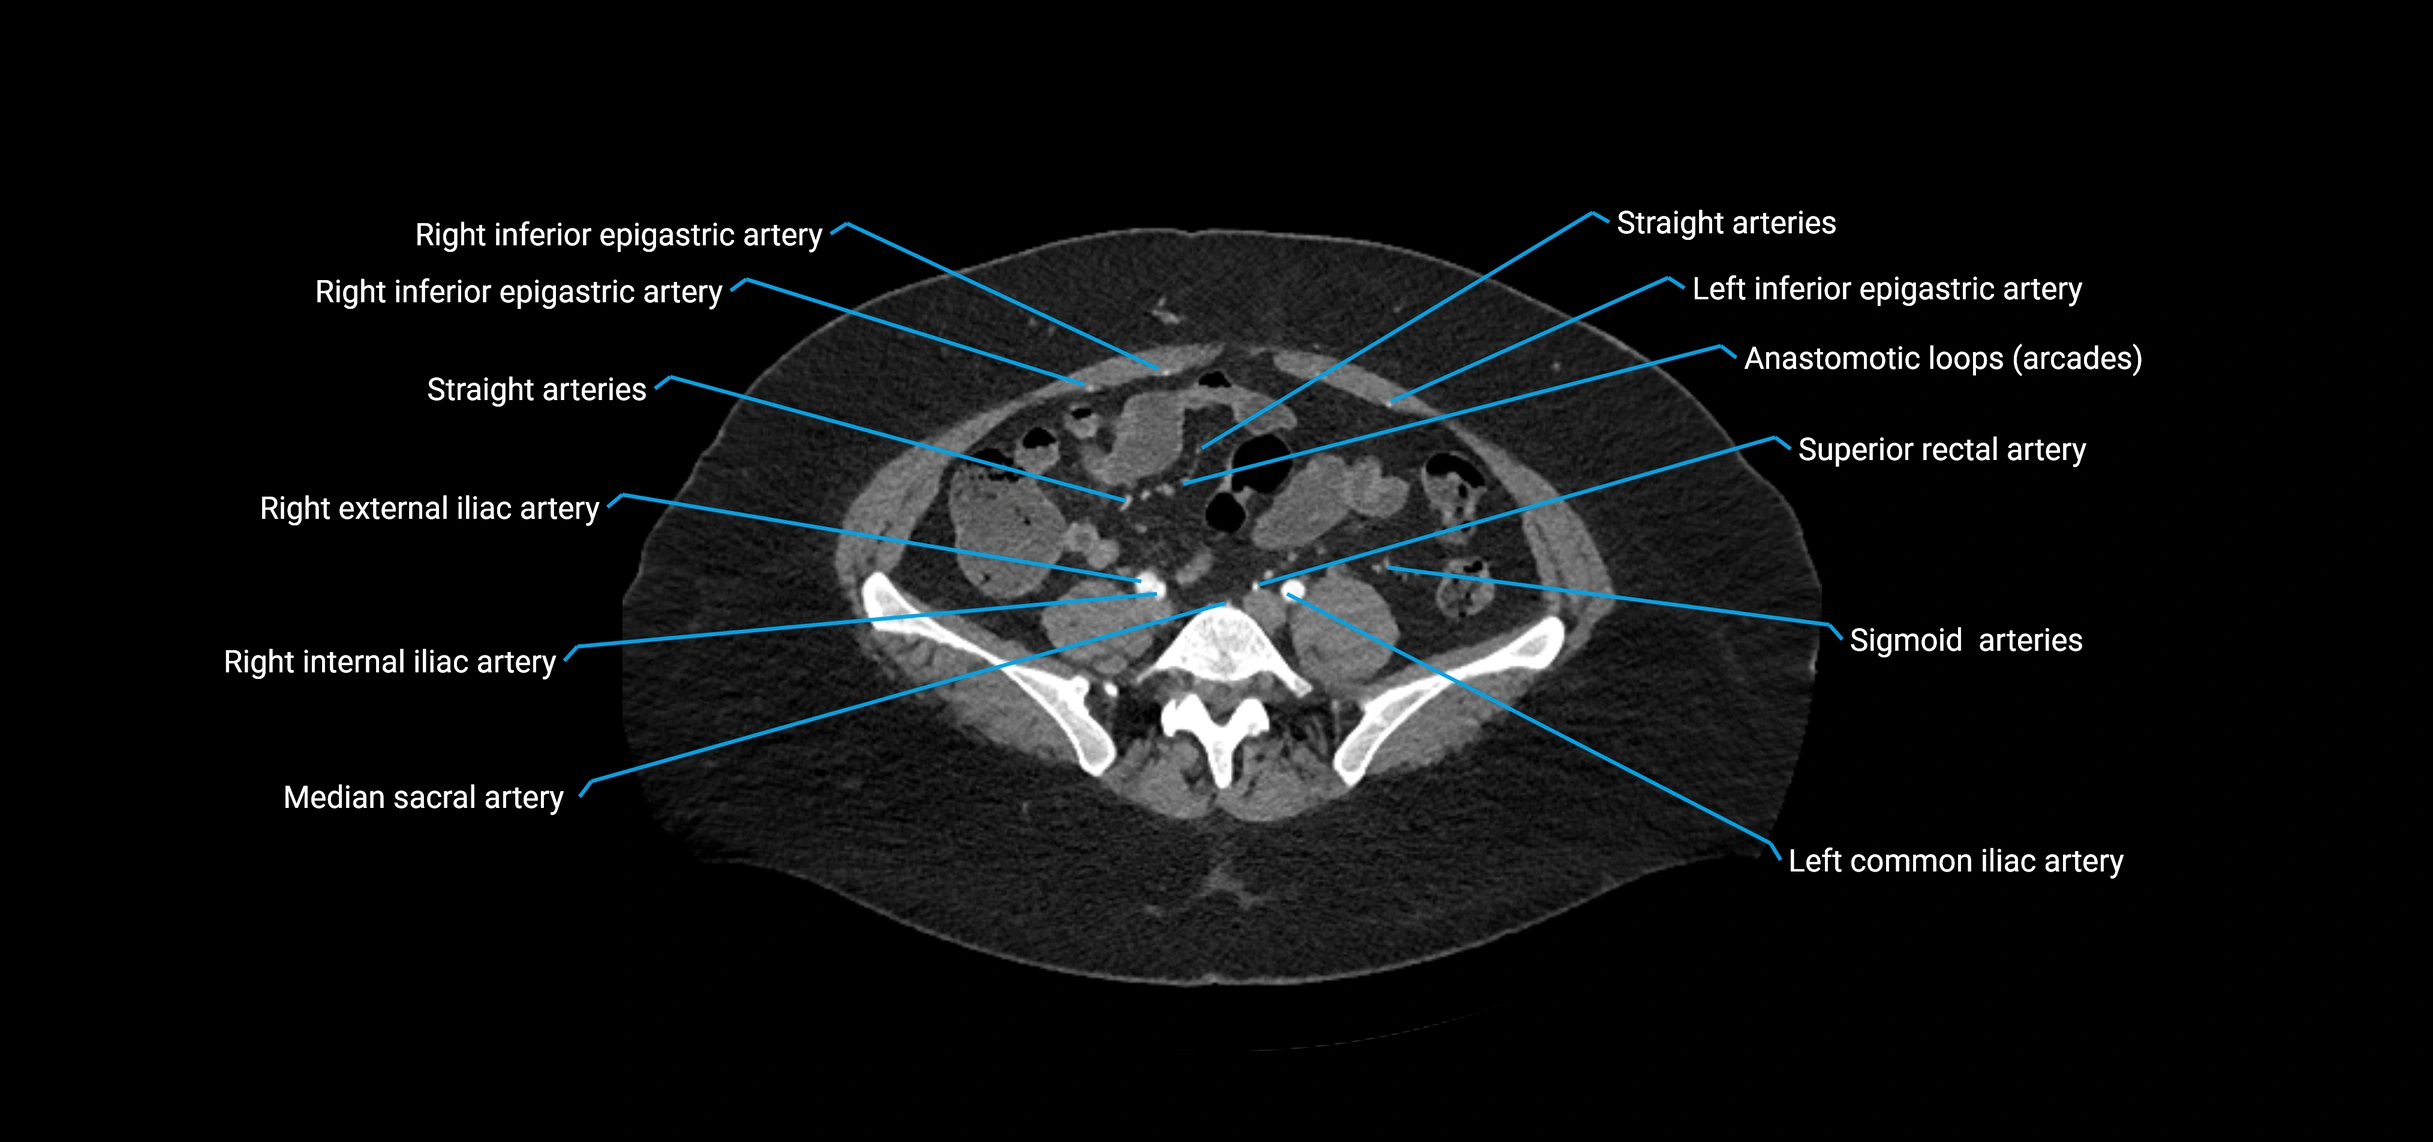

CT images

image